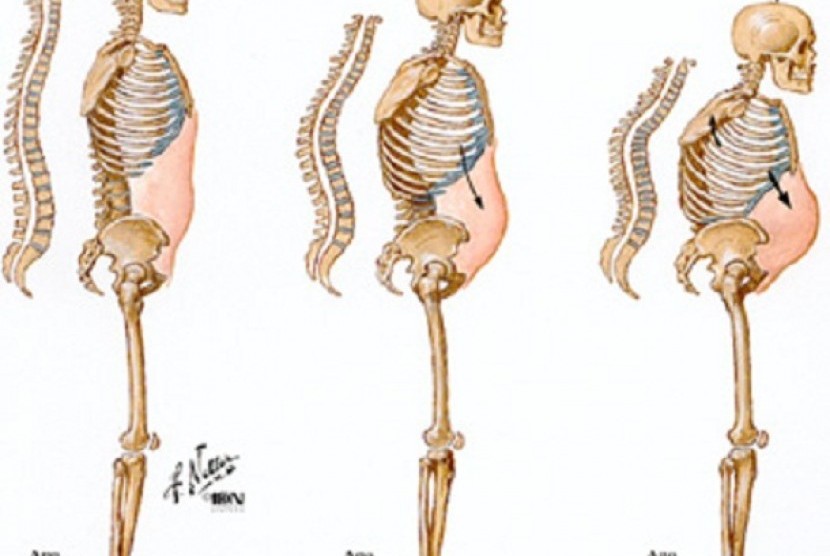

Patah Tulang Pasien Osteoporosis Dapat Dicegah | Republika Online

Patah Tulang Pasien Osteoporosis Dapat Dicegah | Republika Online